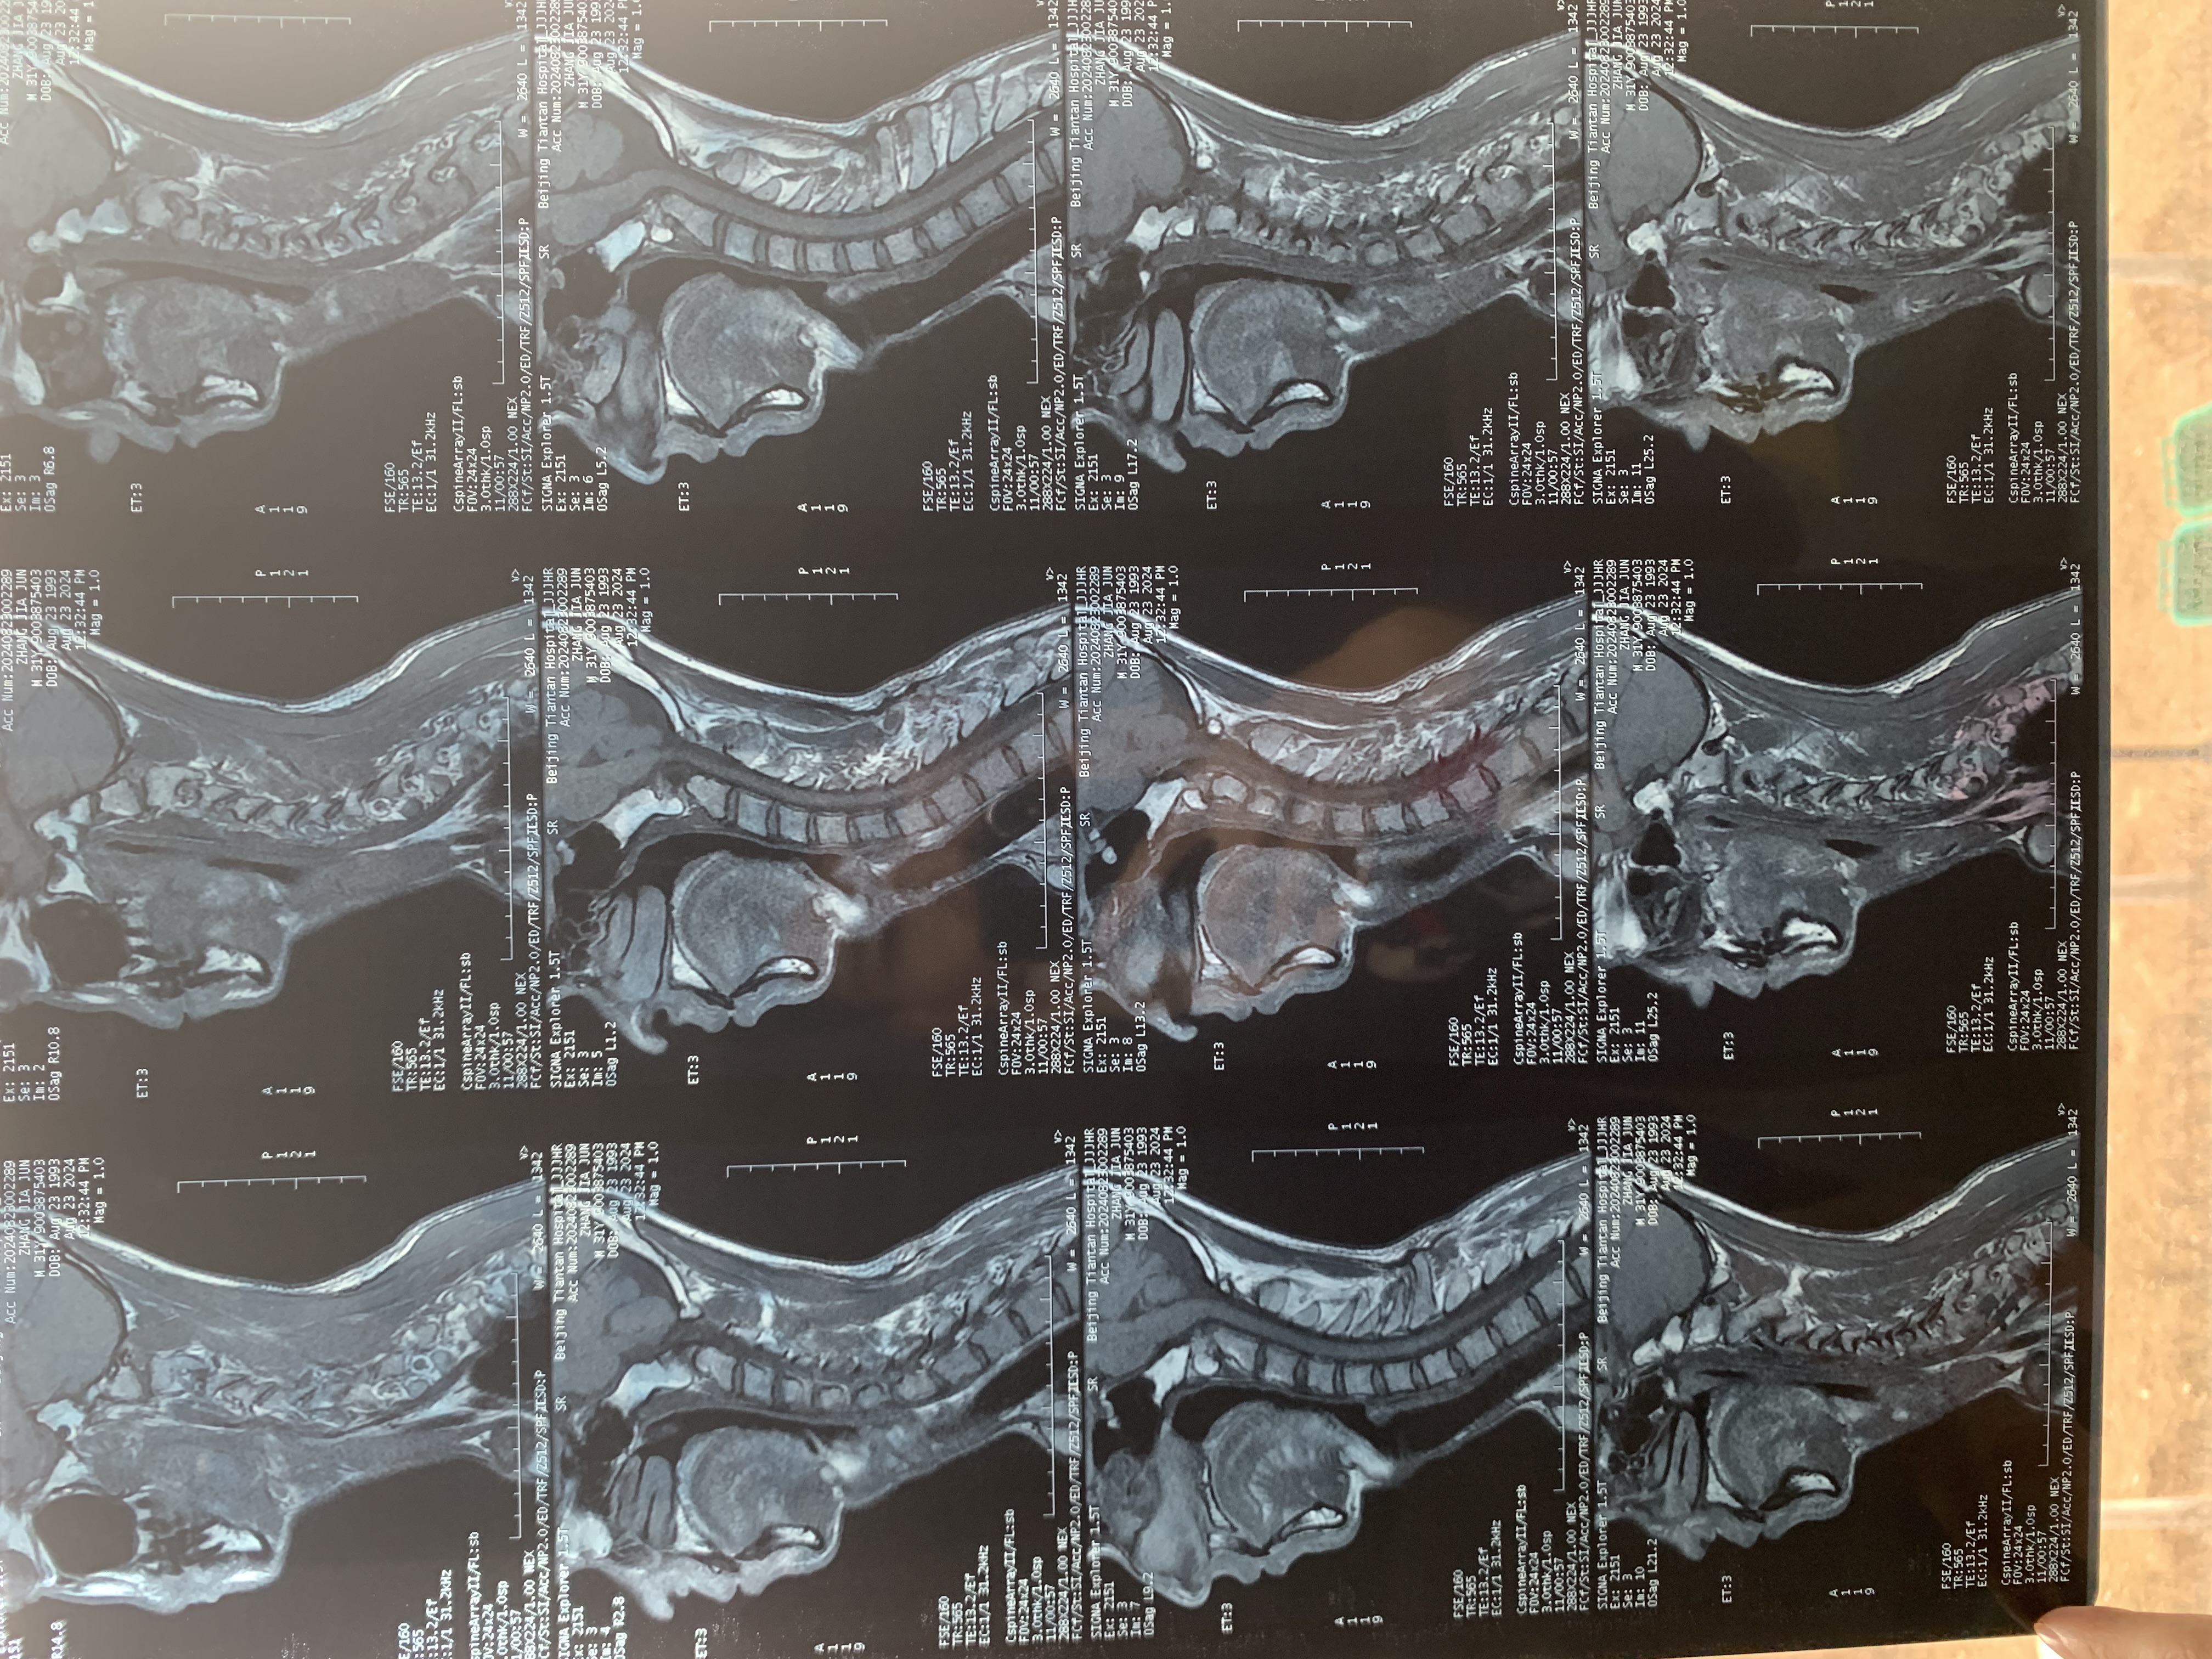

• 2024.12.13,去北京拍片,当天走路有点多,感觉脑袋里面疼。影像报告脱位和颅底凹陷都还在,影像如下: